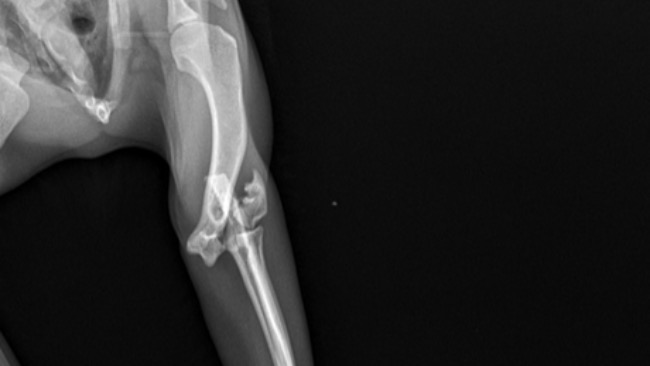

Dyzio to najbadziej wdzięczny kotek jakiegokolwiek spotkałam, jest u nas już rok i nie wyobrażam sobie dalszego życia bez niego. Niefortunne sytuacje zdążają się na codzień, ale niestety w tym przypadku musimy prosić o waszą pomoc. Dyzio wypadł z 3 piętra, oczywiście każde okna mamy zabezpieczone w razie takich sytuacji, jednak właśnie po to aby wymienić siatkę, ponieważ się porwała trzeba było ją zdjąć, kotek najprawdopodobniej zainteresował się jakimś nisko lecącym ptakiem bądź się poślizgnął i spadł. Połamał sobie łapkę tak że sam gips nie wystarczał a operacja byla konieczna aby Dyzio nie musiał chodzić bez łapki. Czeka go teraz długa rekonwalescencja i jeszcze więcej wizyt u weterynarza. Przez trudność zabiegu kwota też nie jest łatwa do zdobycia. Mamy trudną sytuacje finansową dlatego byłyśmy zmuszone do założenia zbiórki. Każdy grosz się liczy aby spłacić zabieg i wizyty u weterynarza. Bardzo prosimy o waszą pomoc!!!